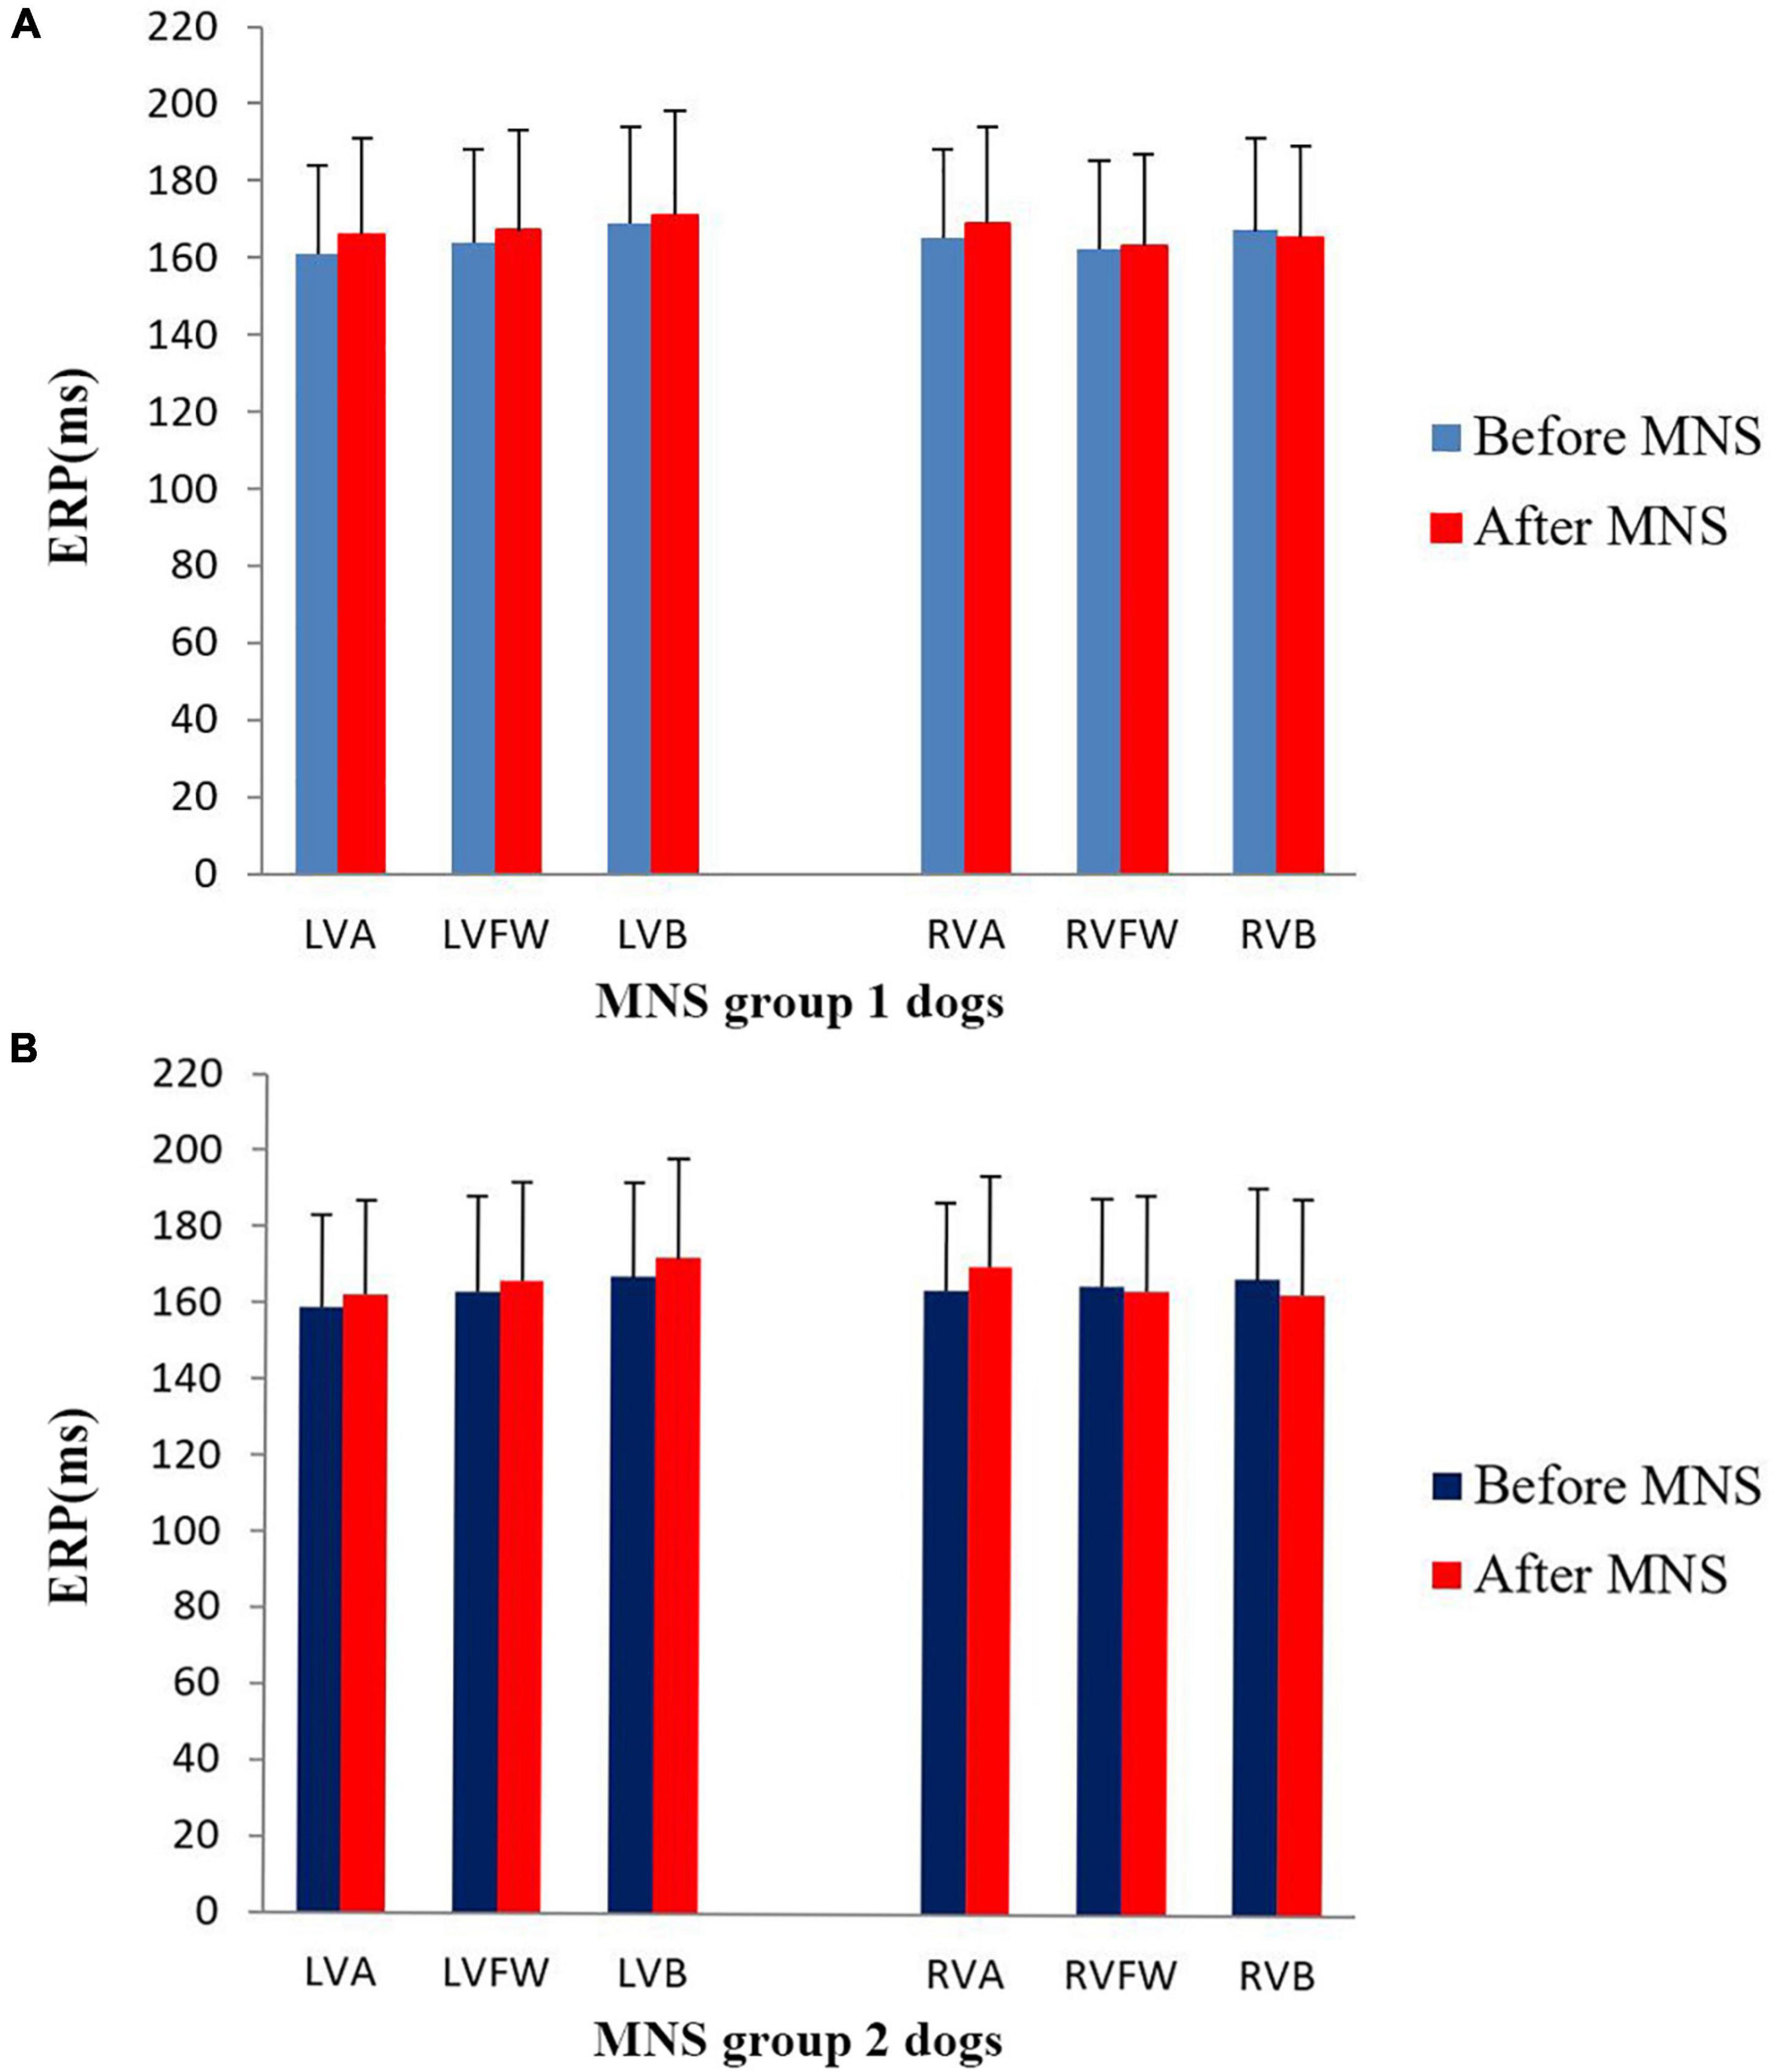

In this study, no significant difference was found in the ventricular ERP between the MNS group 1 and MNS group 2 dogs. Notably, the ERP at RVA was 165 ± 23 ms in the MNS group 1 and 166 ± 19 ms in the MNS group 2, respectively. After 30 min of MNS, the ERPs had no changes at all sites in the MNS group 1 and MNS group 2. For instance, the ERP at the RVA site was 169 ± 25 ms after 30 min of MNS (P > 0.05 for all) (Figure 5). Dispersion of ERP had no significant difference between baseline and after 30 min of MNS in the MNS group 1 and MNS group 2 dogs. Programmed ventricular stimulation induced one episode of VT (defined as five consecutive ventricular beats at a rate of 130 bpm) in one dog in MNS groups 1 and 2 and premature ventricular contractions in one dog in MNS group 2 at baseline. After 30 min of MNS, VA was not induced by programmed ventricular stimulation in the two dog groups.

Figure 5. Changes in the ventricular effective refractory period (ERP) before and after median nerve stimulation. (A) MNS group 1 and (B) MNS group 2. No significant difference in the ERP before and after MNS in the MNS group 1 and MNS group 2 dogs. MSN, median nerve stimulation.